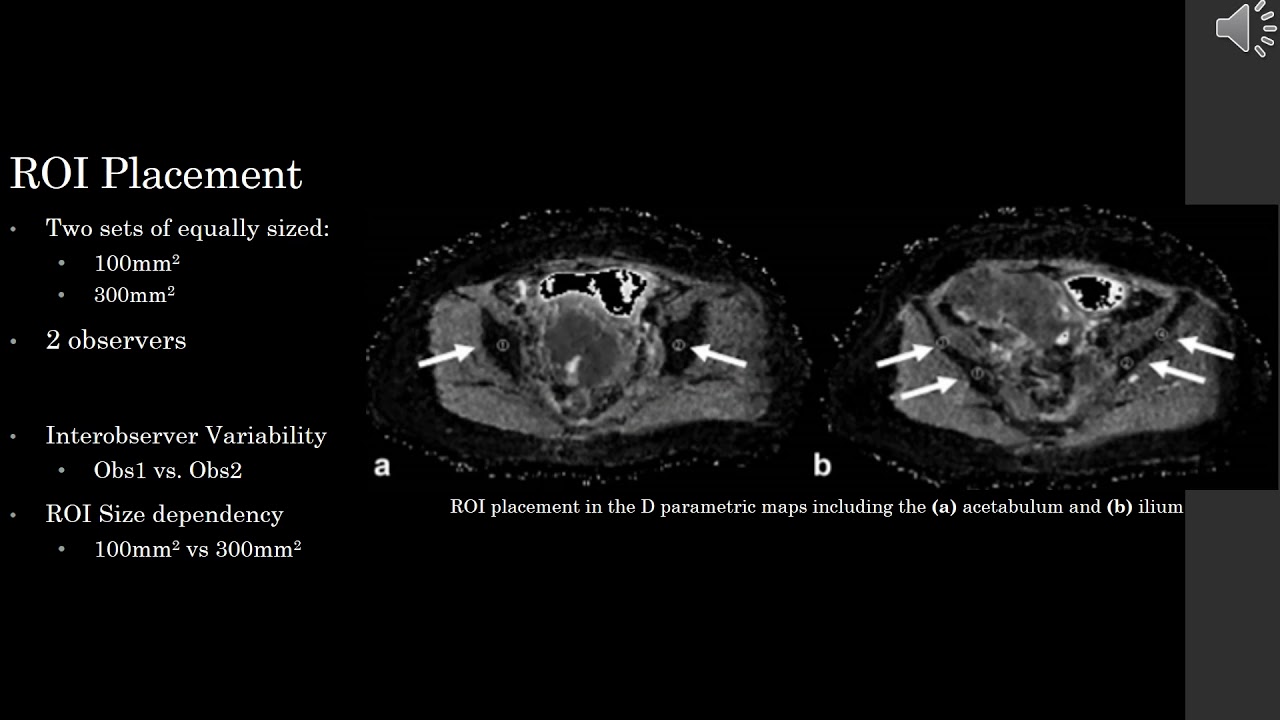

TITLE: Intravoxel incoherent motion MRI assessment of chemoradiation-induced pelvic bone marrow changes in cervical cancer and correlation with hematological toxicity

PURPOSE: To investigate bone marrow changes after chemoradiation (CRT) using intravoxel incoherent motion magnetic resonance imaging (IVIM-MRI) and correlate imaging changes with hematological toxicity (HT) in patients with locally advanced cervical cancer.

MATERIALS AND METHODS: Thirty-nine patients with newly diagnosed cervical cancer were prospectively recruited for two sequential 3.0T IVIM-MRI studies: before treatment (MRI-1) and 3-4 weeks after standardized CRT (MRI-2). The irradiated pelvic bone marrow was outlined as the regions of interest to derive the true diffusion coefficient (D) and perfusion fraction (f) based on a biexponential model. The apparent coefficient diffusion (ADC) was derived using the monoexponential model. Changes in these parameters between MRI-1 and MRI-2 were calculated as ΔD, Δf, and ΔADC. HT was defined accordingly to NCI-CTCAE (v. 4.03) of grade 3 and above. Statistical analysis was performed using Mann-Whitney U-test.